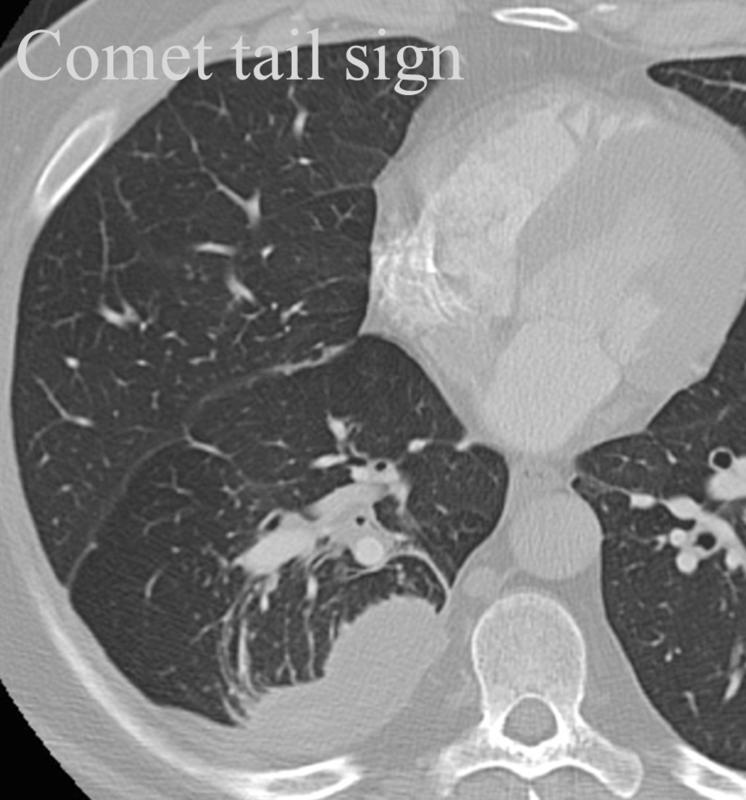

Comet tail sign

Rounded atelectasis